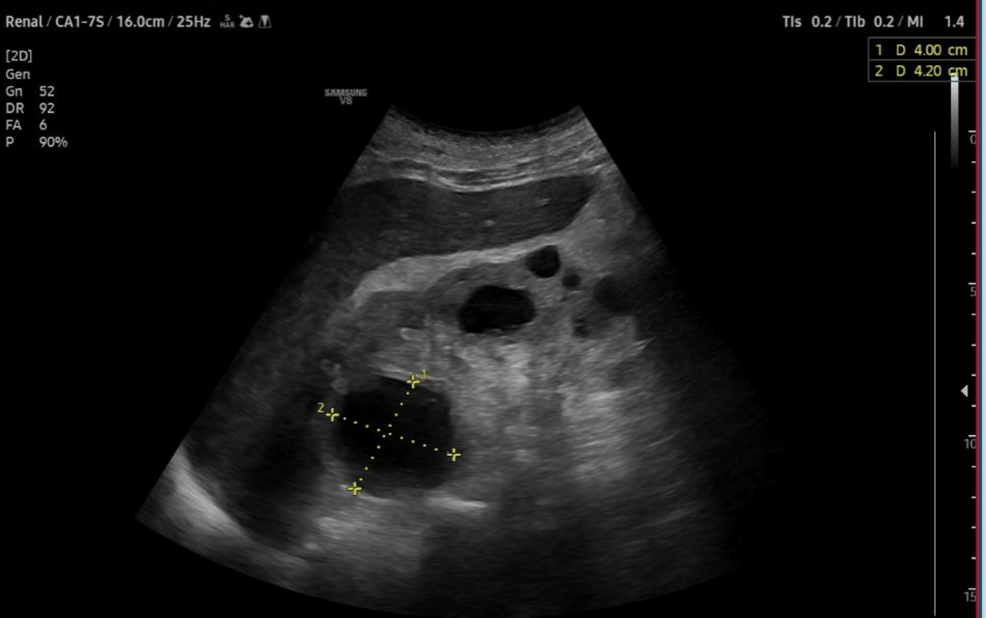

Preoperative evaluation classified the patient as American Society of Anesthesiologists (ASA) physical status 3, reflecting severe systemic disease. The Revised Cardiac Risk Index (RCRI) score indicated Class III, with a major adverse cardiac event risk exceeding 10.1% [4]. Electrocardiography showed sinus rhythm with right bundle branch block (Figure 2), while chest radiography was unremarkable. Airway assessment revealed a Mallampati Class II score, full cervical mobility, and removable partial dentures. Laboratory findings (Table 1) included elevated serum creatinine (4.98 mg/dL), mild hyperkalemia (5.7 mmol/L), mild anemia (hemoglobin of 11.6 g/dL), and a normal international normalized ratio (INR: 1.00). Imaging confirmed the femoral neck fracture, with ultrasonography noting renal cysts (Figure 3) and prostatic enlargement (Figure 4). An echocardiogram was normal (Figure 5). Cardiology consultation advised continuing bisoprolol, resuming aspirin postoperatively, and bridging anticoagulation with enoxaparin, discontinued 24 hours preoperatively. Recent hemodialysis stabilized electrolytes, optimizing the patient for surgery.